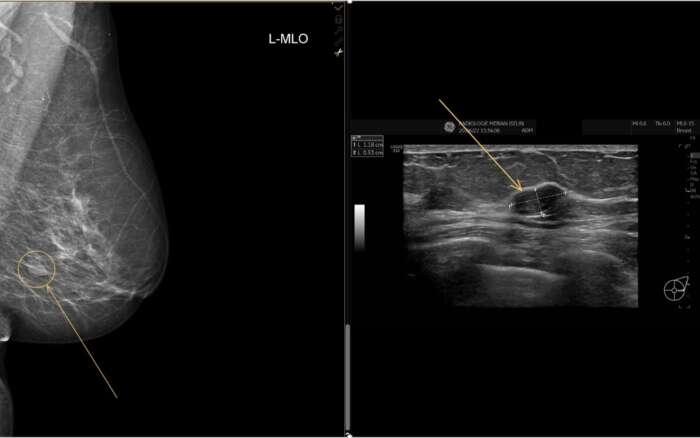

Jasmin tastet schon längere Zeit einen Knoten in ihrer Brust. Sie nimmt das Angebot des Screening-Programms der Stadt Basel wahr und lässt eine Mammographie in der Radiologie in der Merian Iselin Klinik durchführen – eine Freundin hat ihr den Tipp gegeben, dass hier eine freundliche, familiäre Atmosphäre herrscht und sie sich dort sehr gut aufgehoben fühlte.

Schon wenige Tage nach der Mammographie wird sie von ihrer Gynäkologin kontaktiert und erneut in die Merian Iselin Klinik zur weiteren Abklärung geschickt. Die Radiologie in der Merian Iselin Klinik bietet alle essenziellen weiteren spezialisierten Abklärungen der Senologie (Brustbildgebung) an. Jasmin wird von der medizinischen Technologin für Radiologie (MTR) empfangen.

Die Radiologin beschreibt ihr den Grund der Nachuntersuchung, macht einen Ultraschall und erklärt ihr verständlich, dass eine Gewebeprobe entnommen werden muss. Auch das kann direkt hier erfolgen, insofern das die Patientin und die zuweisende Gynäkologin wünschen. Nur wenige Tage darauf trifft Jasmin erneut auf die Radiologin, welche die Biopsie (Gewebeentnahme) durchführt. Jasmin wird nach Erhalt der Ergebnisse ihre Gynäkologin treffen, um die Resultate und das weitere Vorgehen zu besprechen. Glücklicherweise handelte es sich um ein Fibroadenom – einen gutartigen Befund.

Die Brustbildgebung mit Mammographie, Sonographie (Ultraschall), ultraschallgezielter Biopsie und Magnetresonanztomographie (MRT) stellt nur eines unserer weiteren Fachgebiete dar, welches im ersten Untergeschoss der Merian Iselin Klinik angeboten werden.